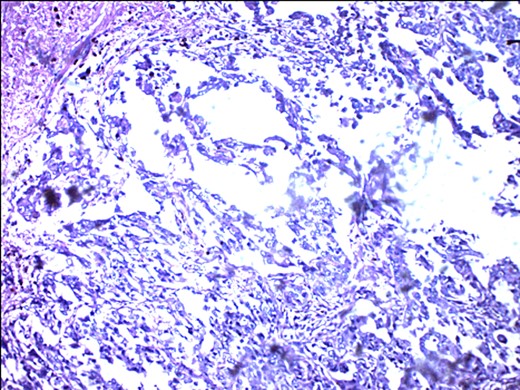

ER negativity for rabbit monoclonal antibodies. Few stromal cells are positive black.

PR-negative immunohistochemistry typing with rabbit progesterone antibodies.